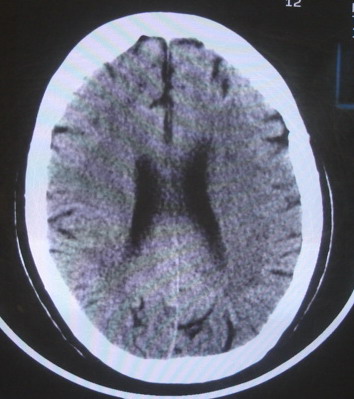

女  67岁 双下肢无力,行动不灵便

老年脑

脑萎缩,腔隙性脑梗塞.

支持老年脑改变。

脑白质病;脑委

右顶叶腔梗

双侧额桥束及左侧脑室旁多发腔梗塞+老年性脑改变

多发腔梗、老年性脑改变、脑白质异常。